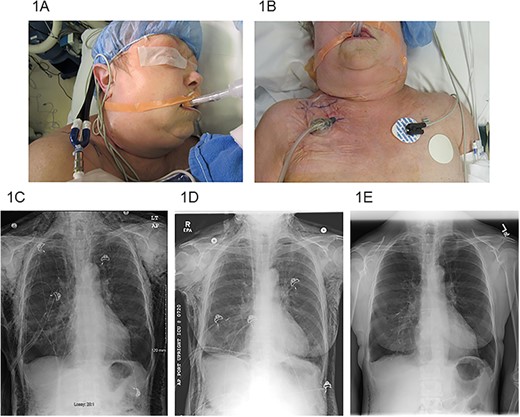

A 5-cm incision was made 2 cm below the clavicle on the ipsilateral side of the thoracic procedure under local anesthesia at the bedside. The incision was deepened through both the subcutaneous tissue and the pectoralis major fascia. Frequently, bubbling was encountered in the wound as the subcutaneous tissues started immediately decompressing. A black wound VAC sponge was cut to size and placed within the wound (Fig. 1A and B). The included plastic sheeting was used to form an adequate seal and suction was applied to −125 mm Hg (V.A.C.ULTA™ system while in-patient, then switched to the ACTIV.A.C.™ system at discharge, KCL/3M, 3M Center, St Paul, MN 55144-1000, USA). Once the wound VAC was placed it was very well tolerated, and only minimal pain medication was required. Sponge and dressing changes were performed twice a week until removal. After the SE had resolved, the wound VAC was removed in the clinic. Upon removal, nice granulation tissue was present and the wound was loosely adapted by interrupted sutures. All wounds healed without complications and the sutures were removed 7–10 days later.

(A) SE extending to the periorbital region, (B) right infraclavicular incision location with VAC dressing, (C) pre-operative chest X-ray, (D) chest X-ray post-operative day #3 after VAC placement and (E) chest X-ray post-operative day #22 after VAC placement.